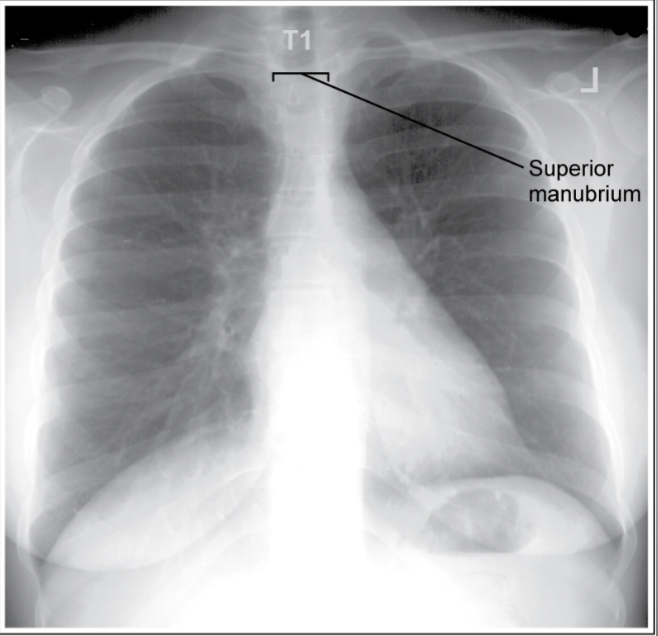

PA chest

inaccurate image

superior MCP tilted anteriorly